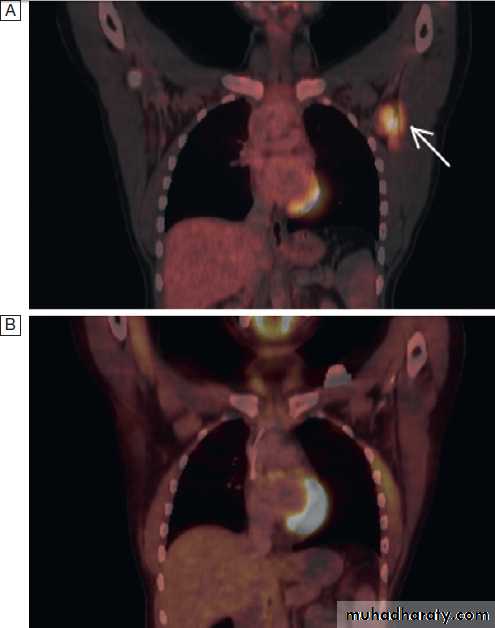

Positron emission tomography

Positron emission tomography (PET) visualises metabolicactivity of tumour cells and is widely used, often

in combination with CT (PET-CT), to evaluate patients with various cancers, including lung cancer and lymphoma

(Fig.). It can accurately assess the severity

and spread of cancer by detecting tumour metabolic

activity following injection of small amounts of radioactive

tracers such as fluorodeoxyglucose (FDG). In

addition to having a role in diagnosis, PET can also be

used in some patients to assess treatment response.

PET-CT images.

A There is a neoplastic lesion in the leftaxilla, evidenced by the increased uptake of FDG traces.

B Imaging after

chemotherapy, demonstrating that the abnormal uptake has disappeared

and Indicating a response to treatment.